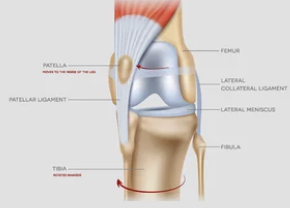

1️⃣ 슬개골 탈구란 무엇일까?

강아지의 무릎(슬개골)은 대퇴골 홈 안에 위치해 있어

다리 움직임을 안정적으로 도와주는 역할을 합니다.

하지만 이 슬개골이 제자리를 벗어나면,

관절이 어긋나면서 통증과 보행 이상이 생기죠.

무릎뼈가 옆으로 ‘툭’ 빠지는 상태예요.